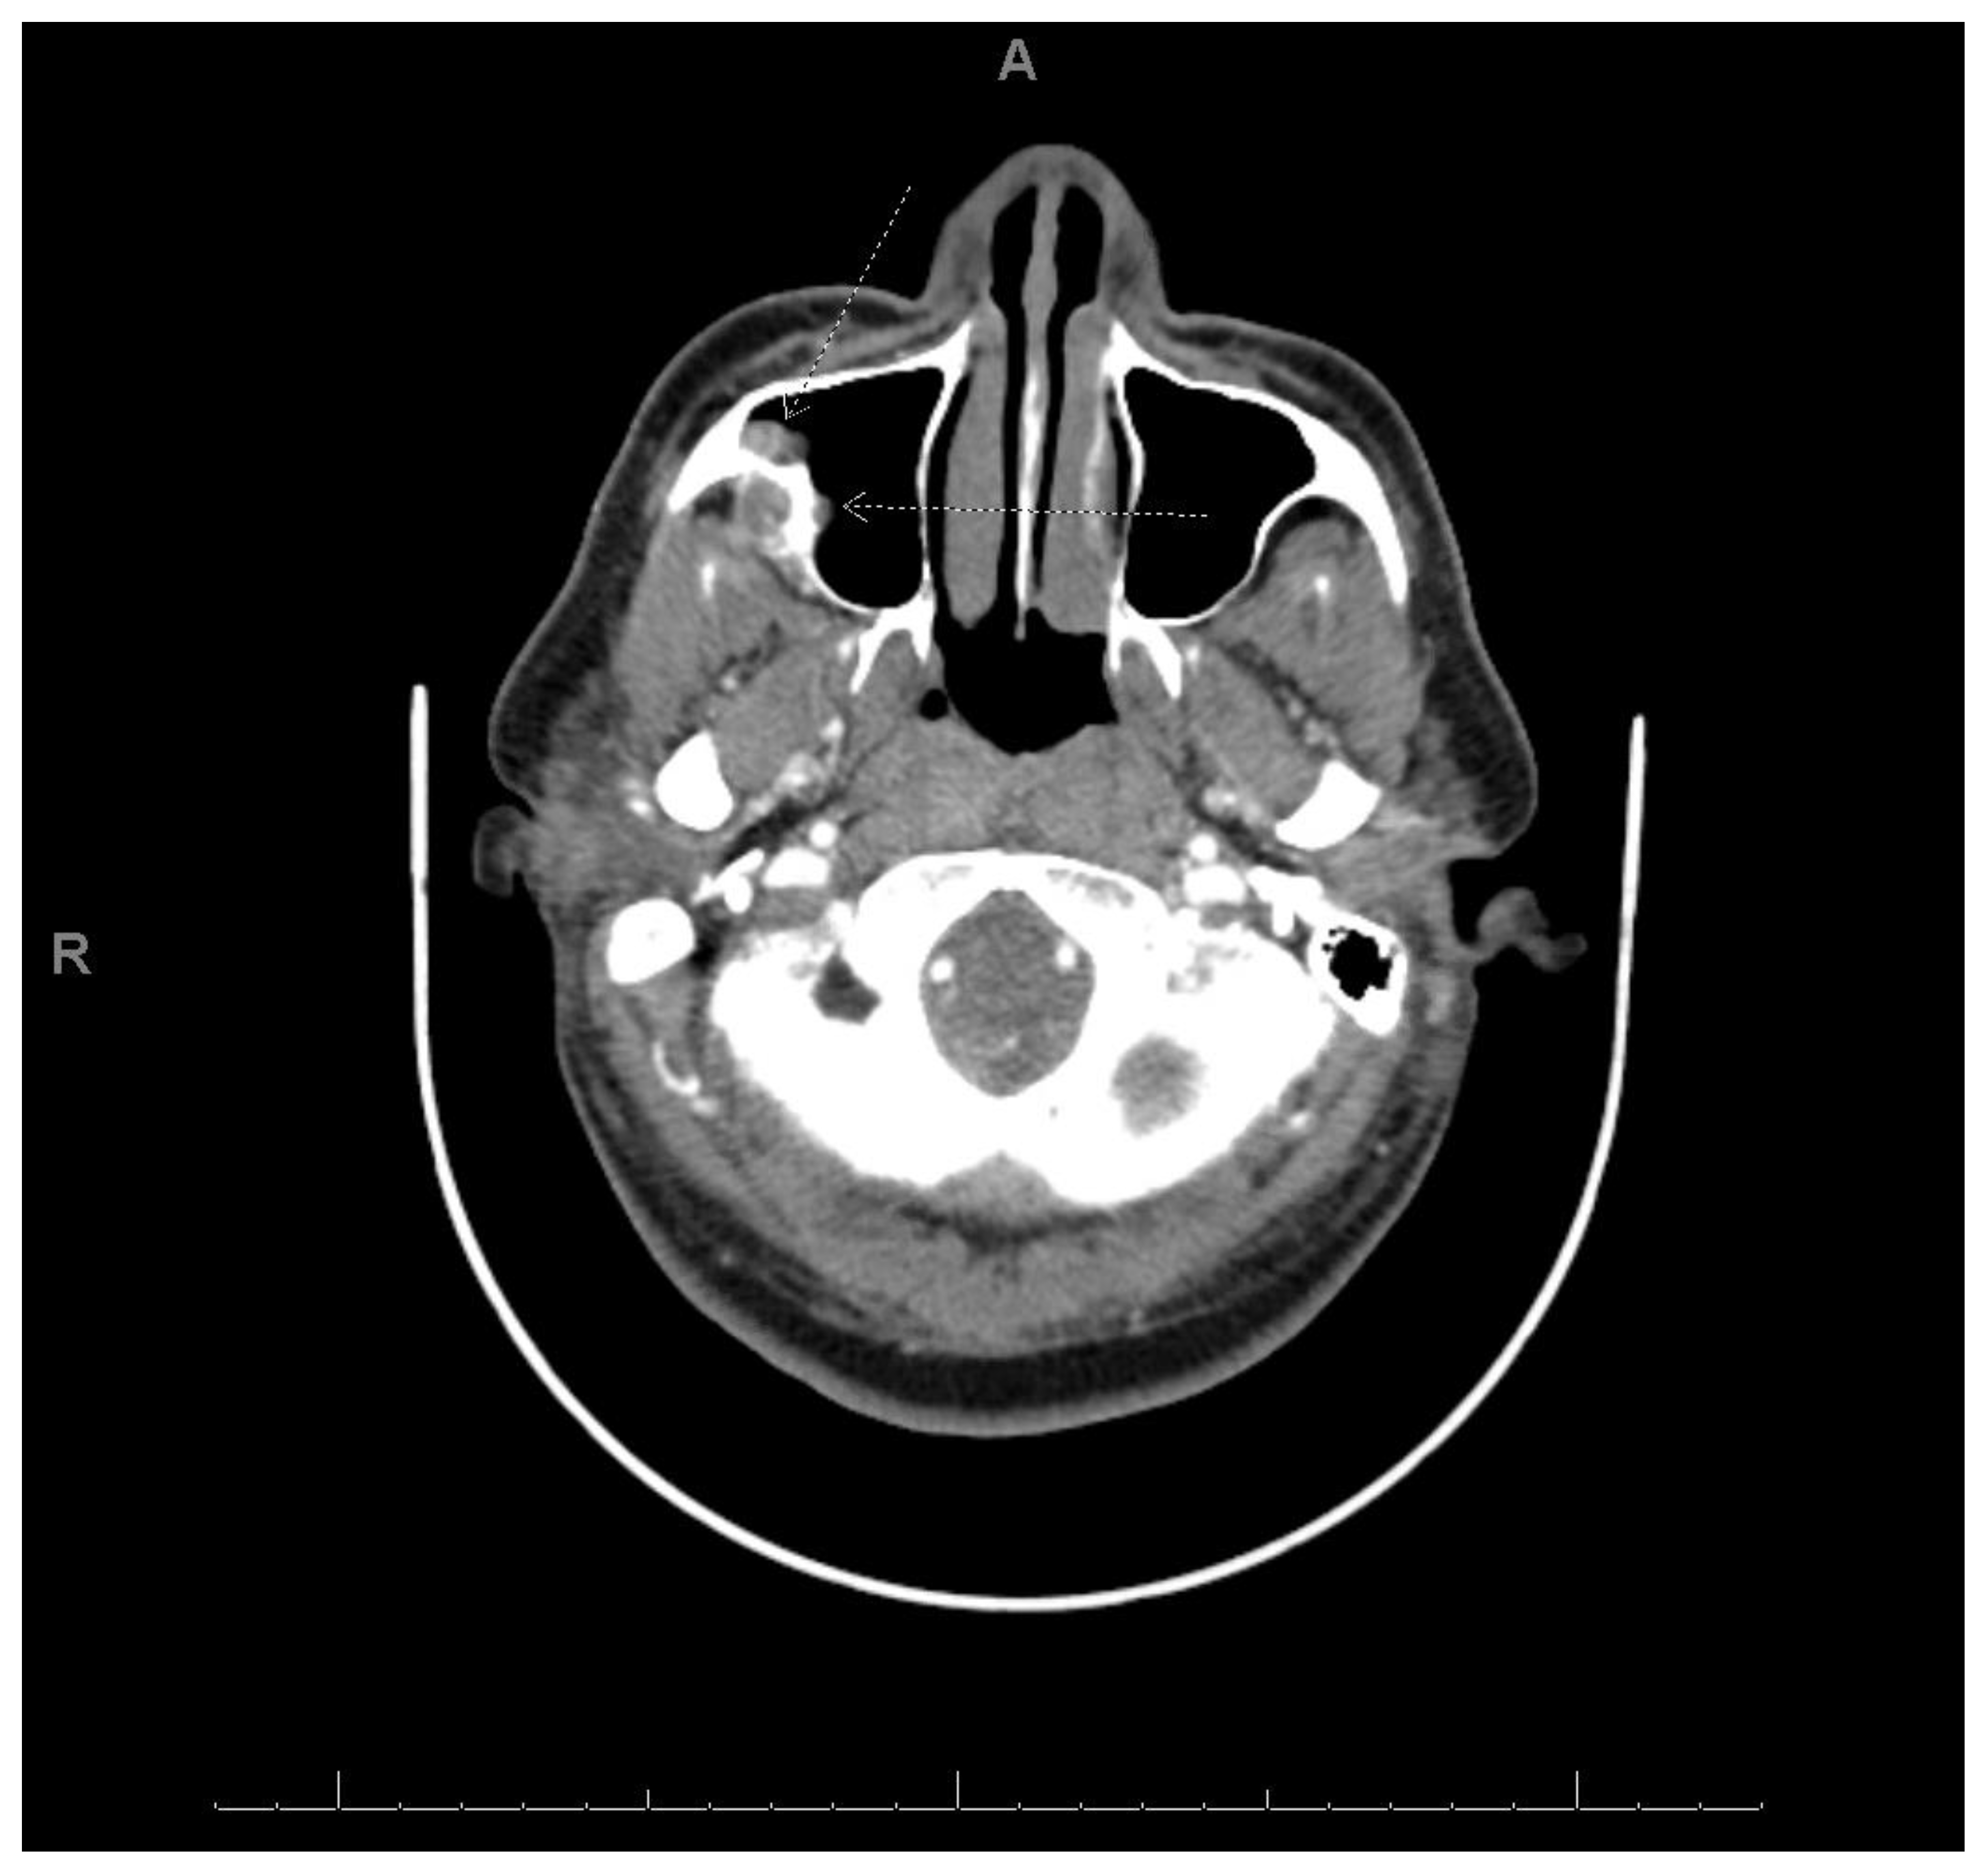

2.3. Case 3